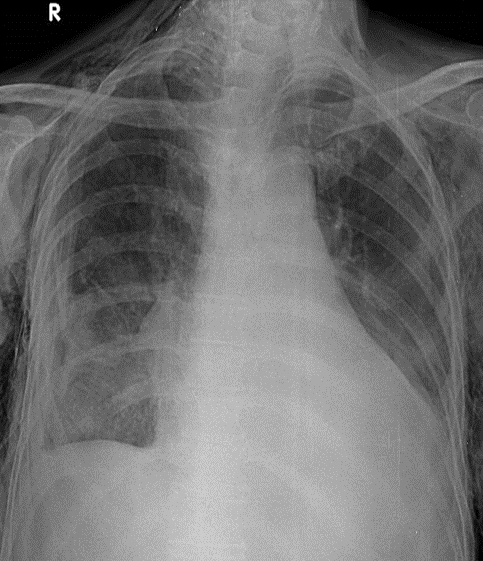

1-Tổn thương phế nang lan tỏa thùy dưới hai phổi=> Viêm phổi, dập phổi 2-Tràn dịch màng phổi (P) 3-Tràn khí màng phổi (T) lượng ít 4-Tim to 5-Gãy cung sườn sau (P): 2->6 6-Tràn khí dưới da thành ngực và vùng cổ hai bên